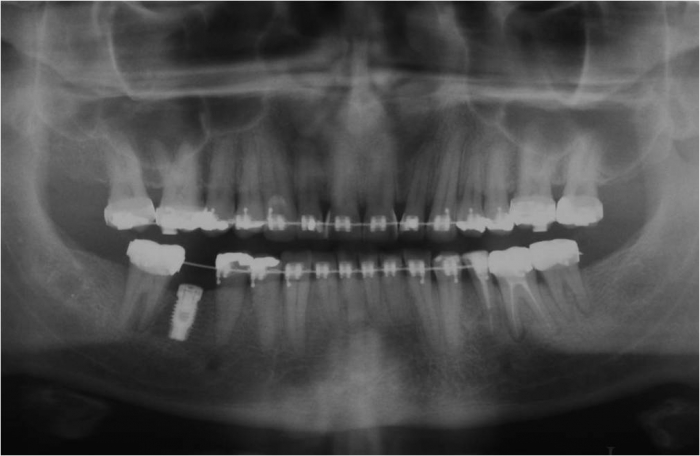

Raio x de controle, 3 anos após a cirurgia